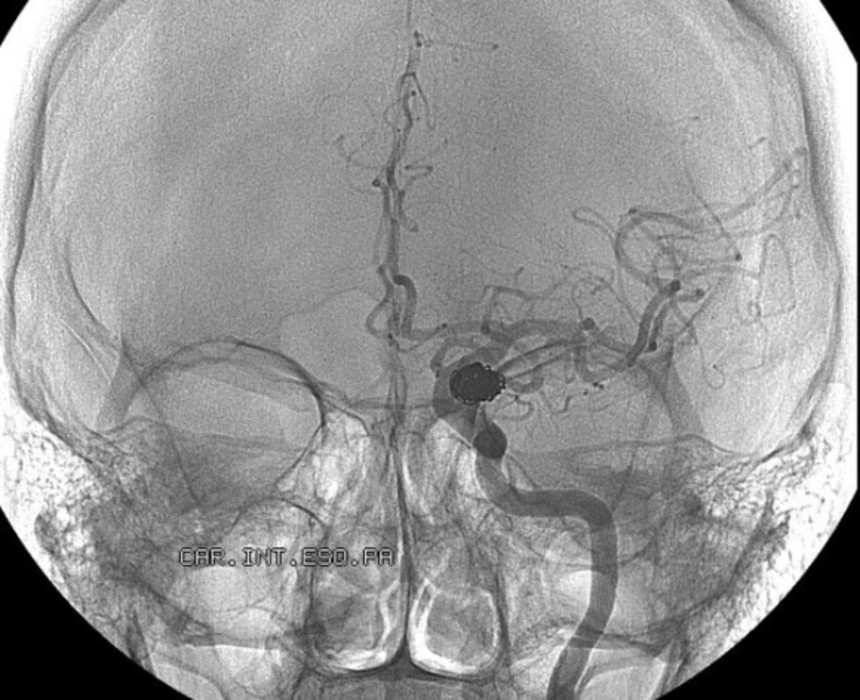

この画像を大きなサイズで見る2012年の初め、32歳のサラ・トムソンは脳へと血液を運ぶ動脈の閉鎖によって脳虚血を引き起こし、10日間も昏睡状態が続いていた。そしてやっと目覚めることができた。